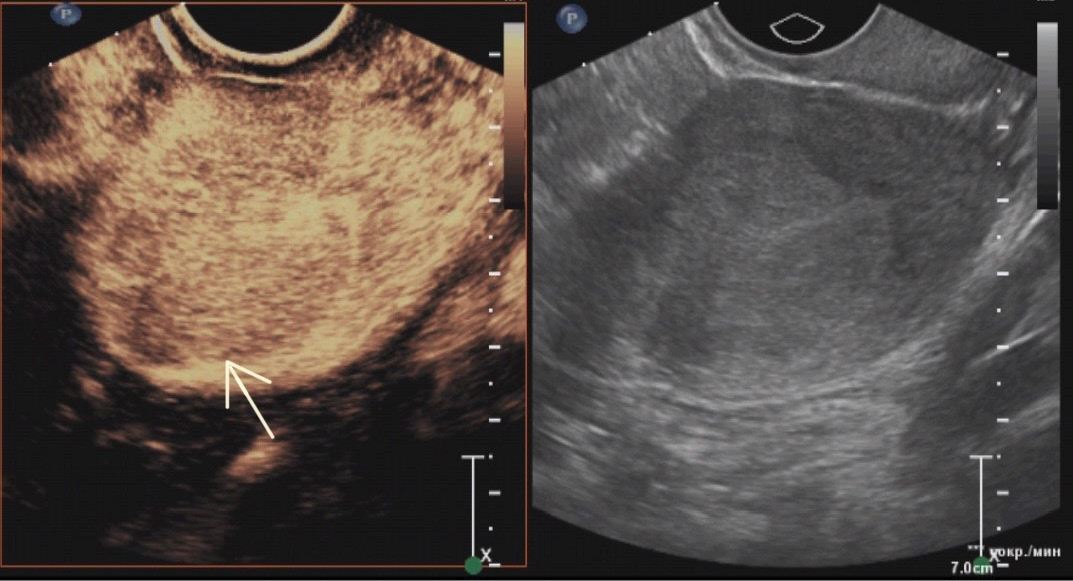

According to our study data (Tables 1 and 2), qualitative signs of contrast enhancement for endometrial cancer are homogeneous contrasting (71.1%), isocontrasting in the arterial phase (81.6%), and hypocontrasting in the venous phase (76.3 %), predominantly simultaneous entry of contrast agent compared with the intact myometrium (79.0%) and its earlier washout (71.1%) (Figs. 1 and 2). The time of the contrast agent entry into the site of endometrial formation, assessed visually by a specialist, varied from 8 s to 24 s from the start of the study (average, 15.16 s; median, 14.5 s).

Fig. 2. Venous phase of contrast in endometrial cancer (hypocontrasting due to earlier leaching of contrast from the tumor compared to intact myometrium): a ― in contrast mode, the arrow shows the contour of the tumor; b ― in the gray scale mode.

The washout time of the contrast agent ranged from 32 to 127 s, the mean value was 48.5 s, and the median was 53.84 s. Tumor contours were distinct in half (50%) of the cases.